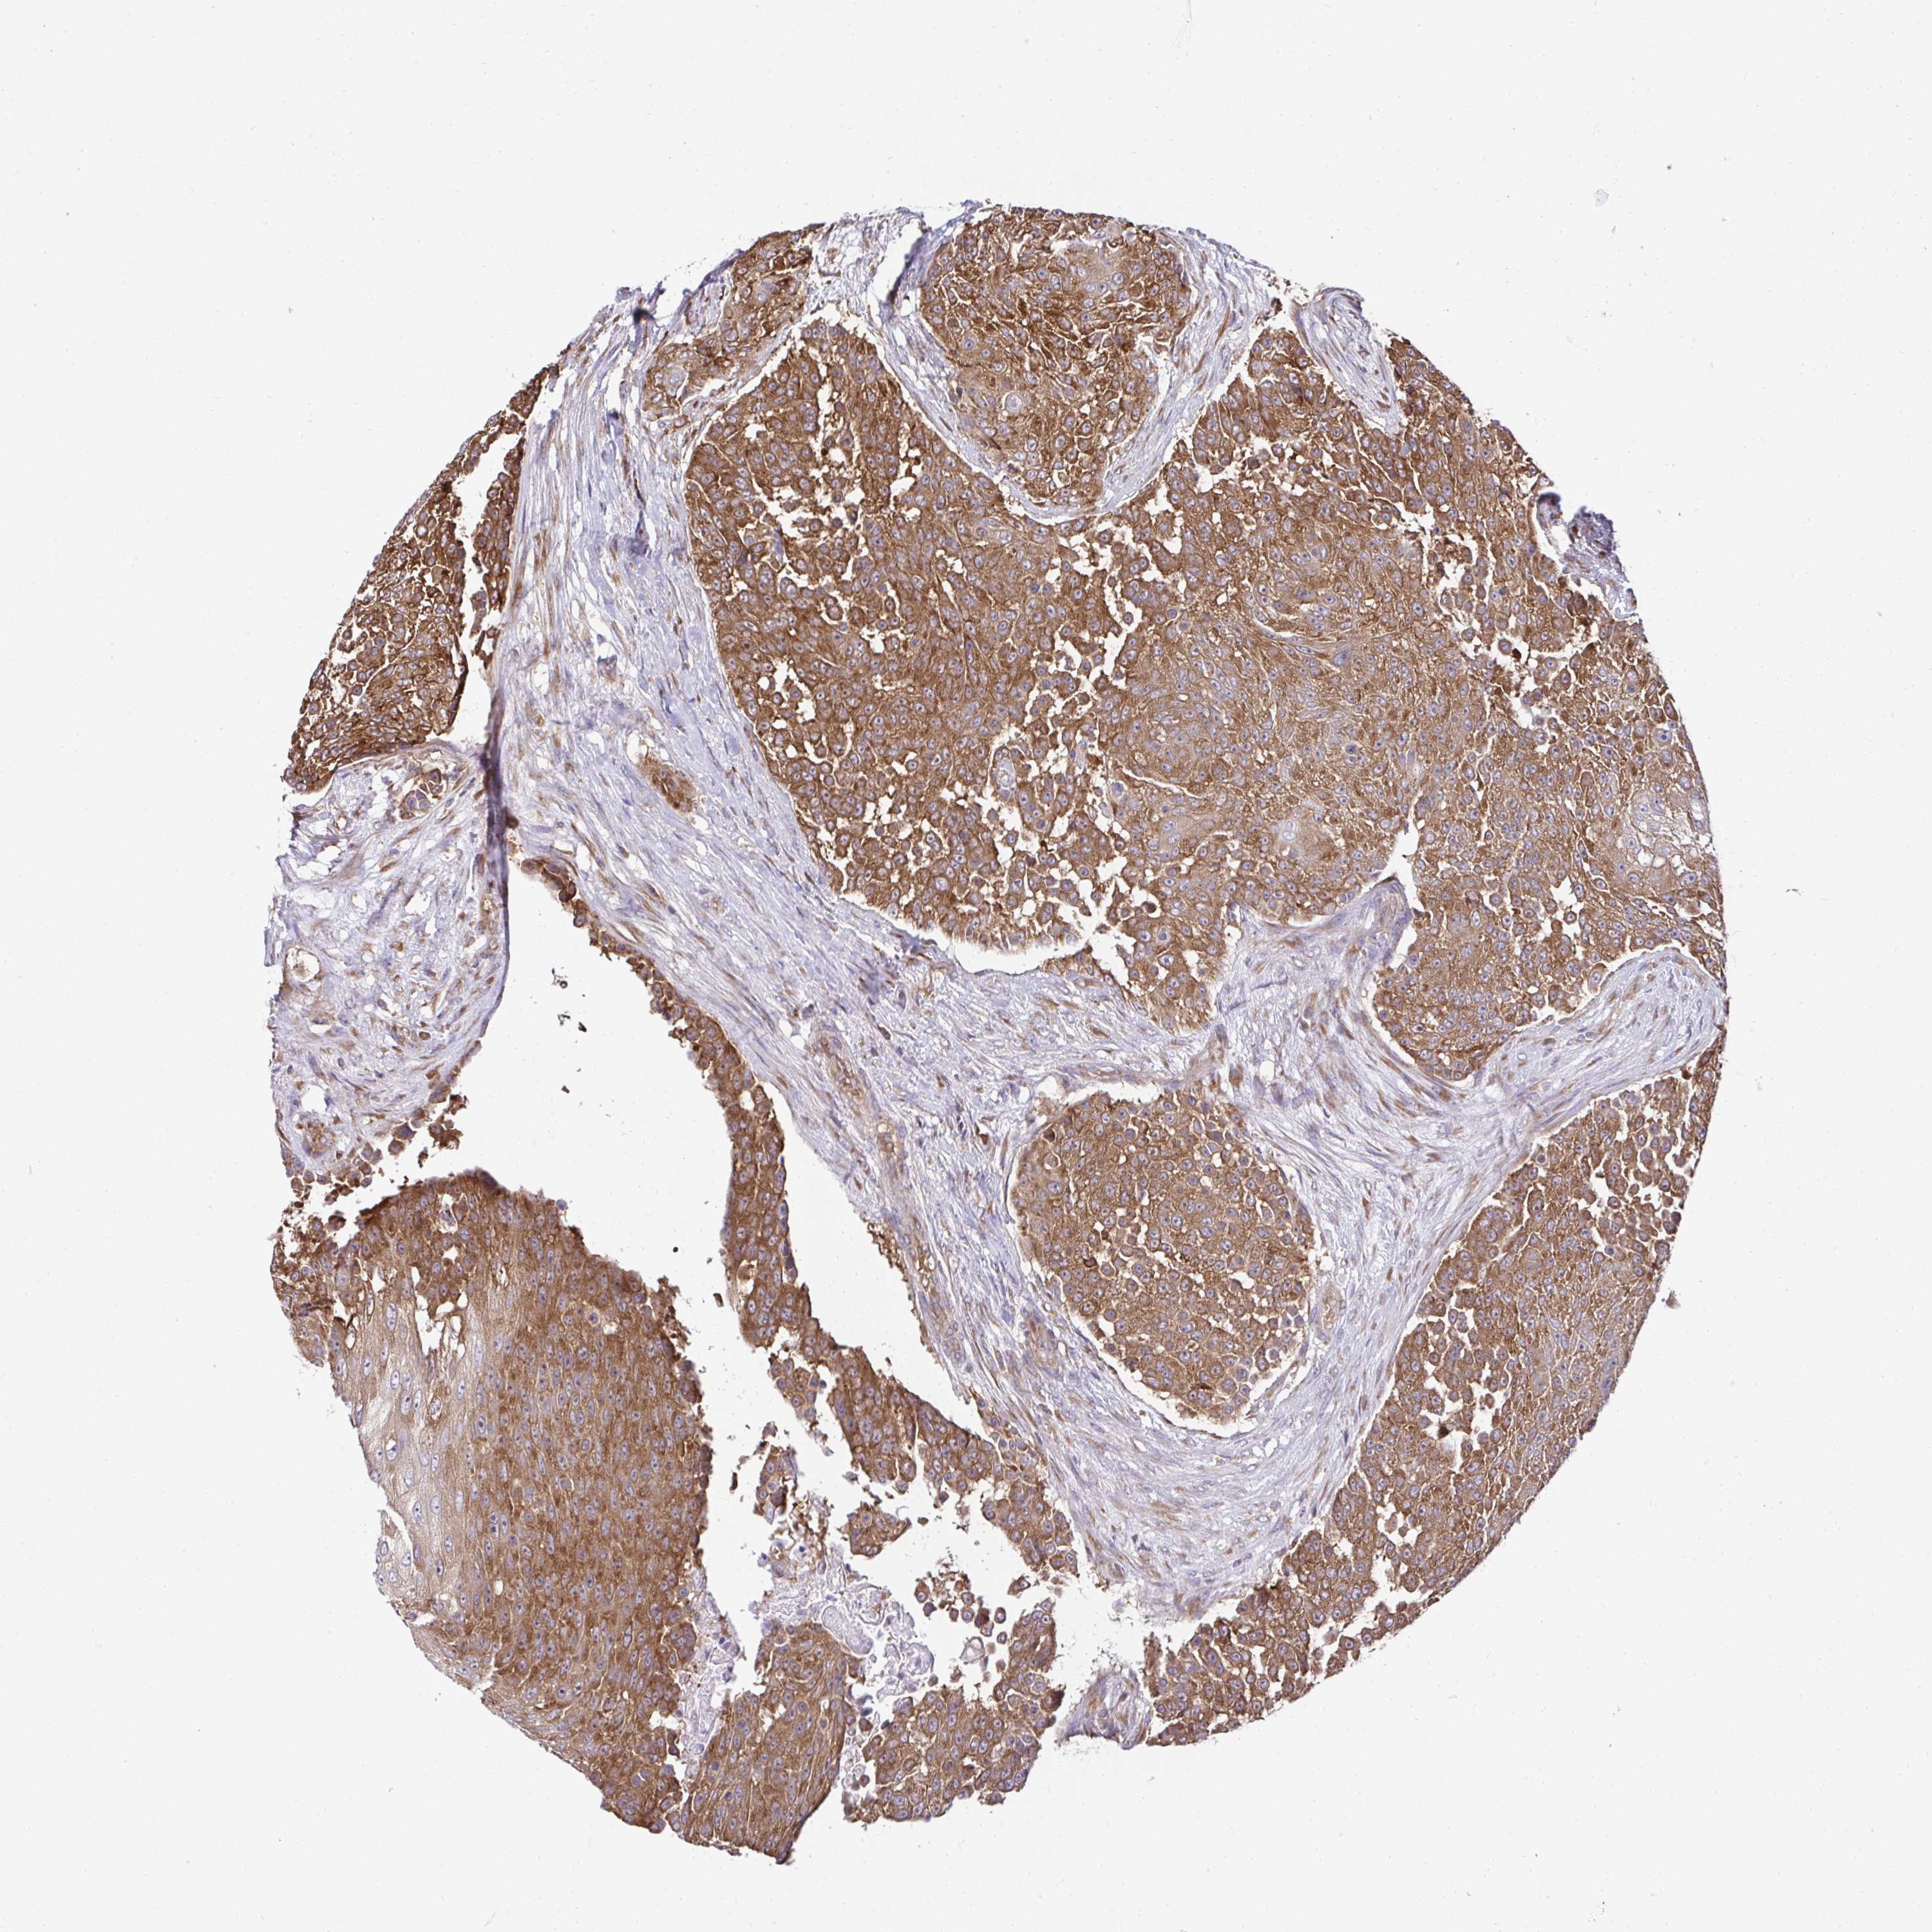

UROTHELIAL CANCER - Protein expressioni

A mouse-over function shows sample information and annotation data. Click on an image to view it in a full screen mode. Samples can be filtered based on level of antibody staining by selecting one or several of the following categories: high, medium, low and not detected. The assay and annotation is described here.

Note that samples used for immunohistochemistry by the Human Protein Atlas do not correspond to samples in the TCGA dataset.

Antibody stainingi

Antibody staining in the annotated cell types in the current human tissue is reported as not detected, low, medium, or high, based on conventional immunohistochemistry profiling in selected tissues. This score is based on the combination of the staining intensity and fraction of stained cells.

Each image is clickable and will lead to virtual microscopy that enables deeper exploration of all samples and also displays staining intensity scores, fraction scores and subcellular localization as well as patient and tissue information for each sample.

Antibody HPA056586

Staining

High

Medium

Low

Not detected

Intensity

Strong

Moderate

Weak

Negative

Quantity

>75%

75%-25%

<25%

None

Location

Nuclear

Cytoplasmic/membranous

Cytoplasmic/membranous,nuclear

Urothelial carcinoma, High grade

Urothelial carcinoma, Low grade